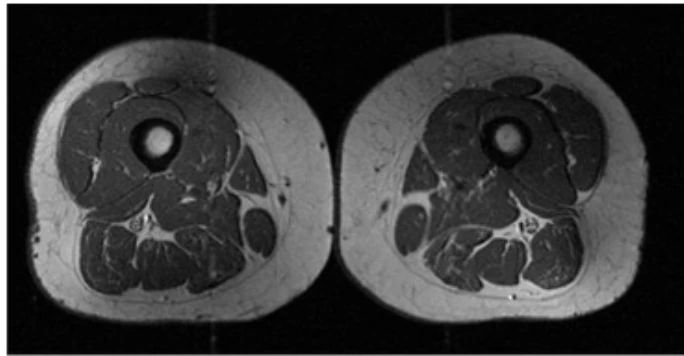

The first image shows the thigh muscles of the woman who ate far fewer UPFs. As you can see, the muscles are lean and defined with little marbling.

An MRI scan was done on each participant’s thighs, then researchers analyzed the scans and graded fat infiltration in the thigh muscles.

The study concluded that people who ate and drank higher amounts of UPFs had far greater intramuscular fat, especially in the thighs.